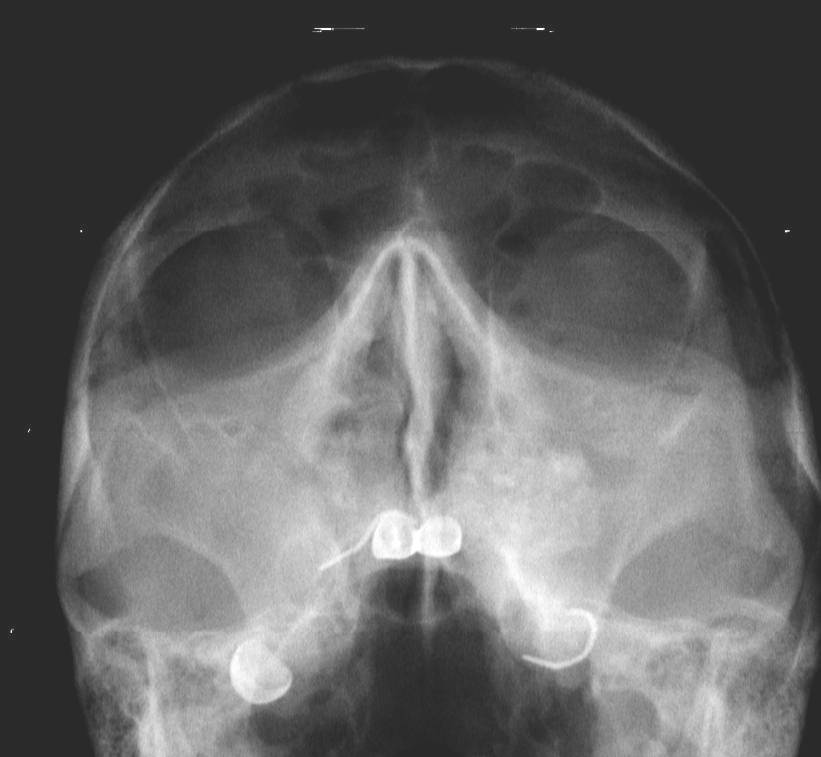

Рис.1 Выраженный воспалительный процесс в верхнечелюстном синусе вызванный разрушенными зубами

При обследовании в клинике ДомоденТ лор-врачом и стоматологом с помощью конусно-лучевой компьютерной томографии выявлен воспалительный процесс, который охватывал всю правую верхнечелюстную пазуху. В полости рта со стороны пазухи обнаружили два разрушенных зуба. (рис.1) Наши специалисты определили, что именно зубы явились причиной гайморита. Объясним, как это связано: Корни верхних боковых зубов находятся близко к гайморовой пазухе, поэтому воспалительный процесс из корневого канала может распространяться на гайморову пазуху.